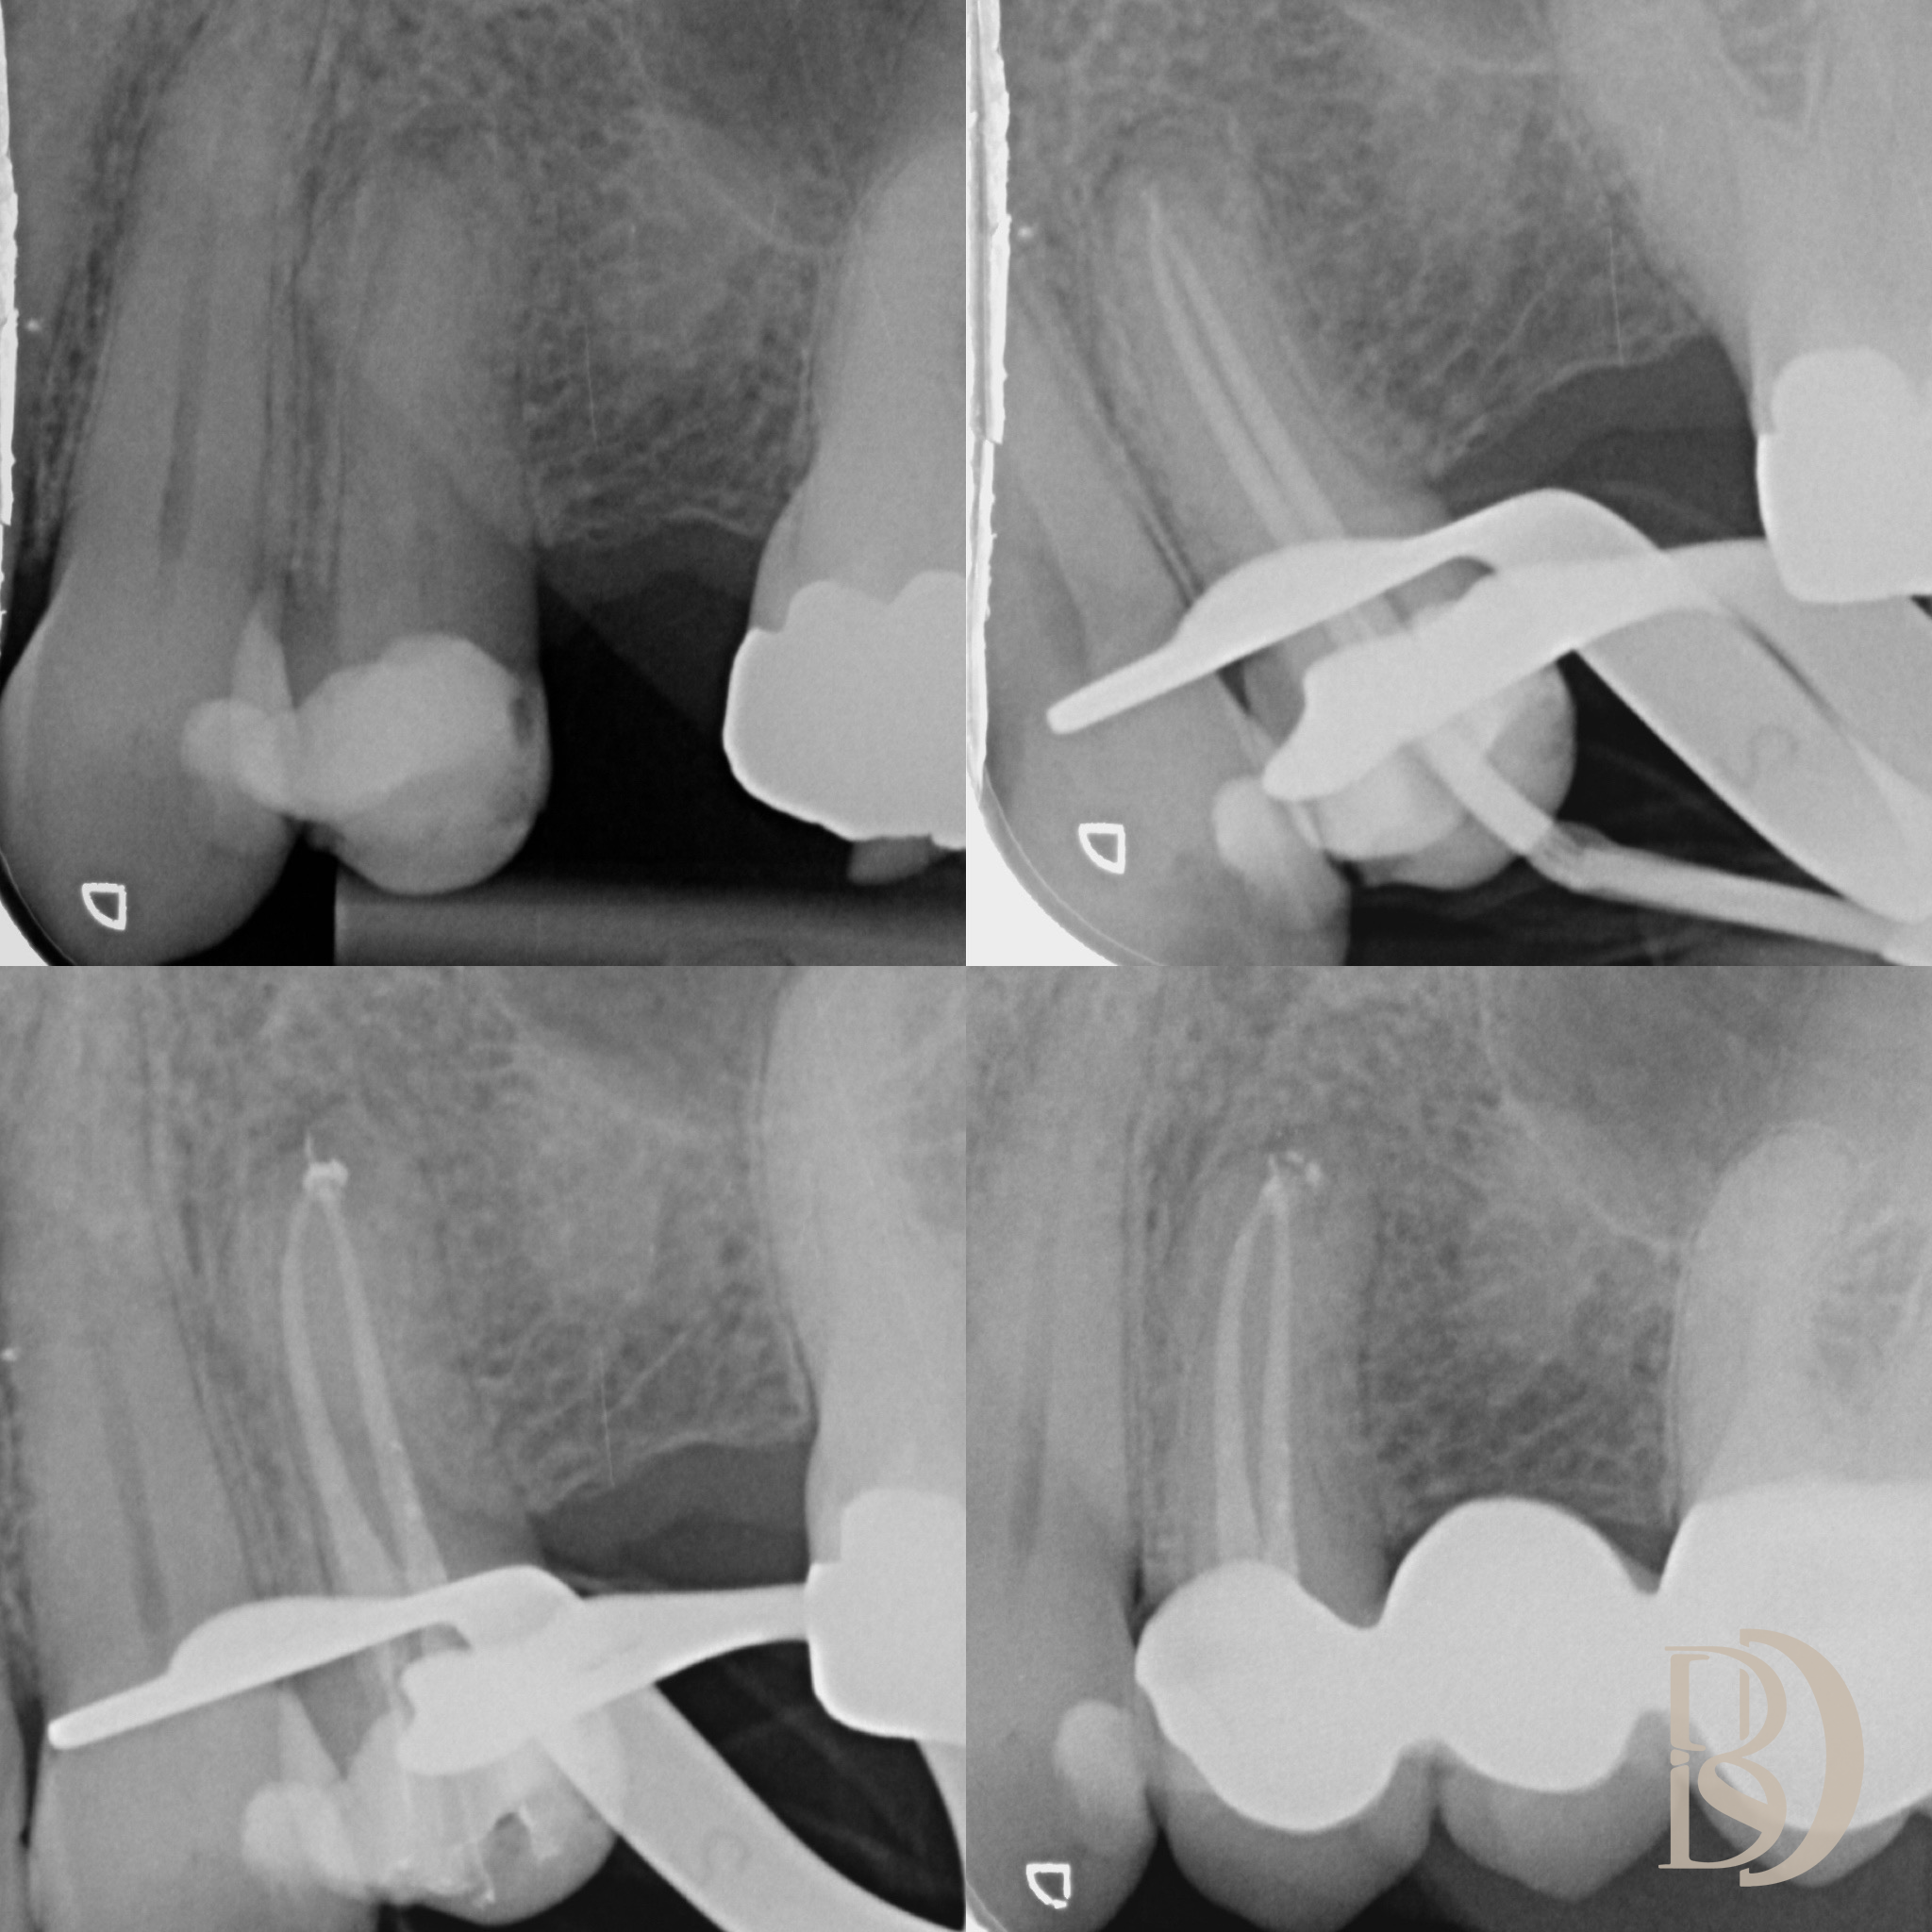

Some examples of Dr Fred’s Endodontic cases:

X-ray images showing dental and endodontic procedures on molar teeth.

Dental X-rays showing tooth root structures and dental instruments in place.